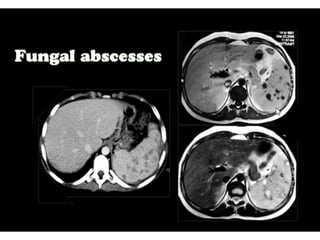

This document discusses the spleen and causes of splenomegaly (enlarged spleen). It begins by thanking radiologists for their assistance. Simple cyst criteria are outlined. Splenogonadal fusion and sarcoidosis are mentioned. The main causes of splenomegaly are then listed, including infections, portal hypertension, hemolytic anemias, hematological malignancies, infiltrative disorders, collagen vascular disorders, and congestive cardiac failure.